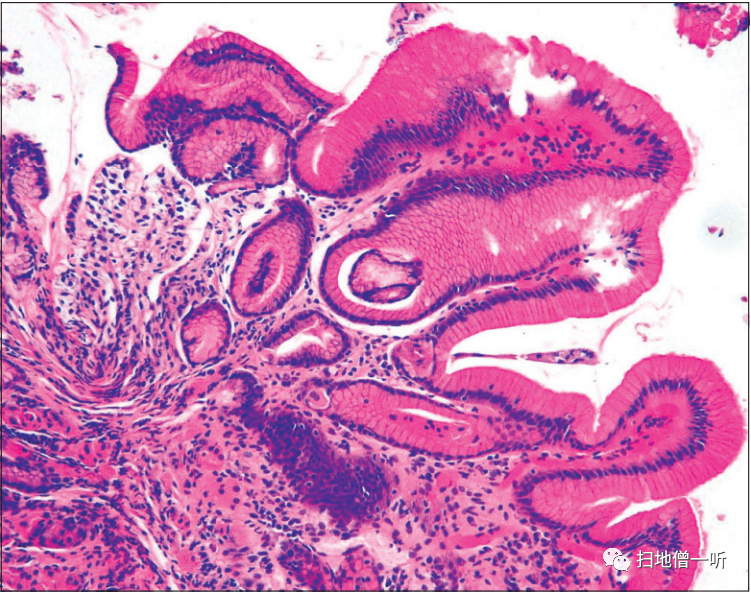

▲病理组织学上,主要由壁细胞构成的胃底腺囊胞状扩张以及壁细胞障碍。

胃底腺息肉是H.pylori阴性者的观察结果,国外的横向研究和队列研究表明,长期服用PPI者的胃底腺息肉增加。而且,在日本的队列研究中,表明了H.pylori阴性者的特征是使用PPI引起的胃底腺息肉增大。PPI中增大的胃底腺息肉的内镜特征是显示出水肿样膨化的多房样形态。在病理组织学上,主要由壁细胞组成的胃底腺有明显的囊胞状扩张所见,伴有类似PCP的壁细胞障碍。

▲在胃底腺息肉(黄色箭头)的活检标本中,确认了壁细胞的增生以及PCP样所见。

因使用PPI而发现胃增生性息肉增大的病例。通过投用PPI/P―CAB,贲门部的增生性息肉显著增大,使用Bonoprazan 20mg时,血清胃泌素值为2820 pg/ml,显示出显著的高值。将Bonoprazan变更为雷贝拉唑后,变更后2周内镜检查发现息肉缩小,血清胃泌素值降低到970pg/ml。在病理组织学上,在增生性息肉中发现了小凹上皮的显著增生性变化,但没有异型性。在附近的胃底腺息肉中,在组织学上发现了PCP样所见。